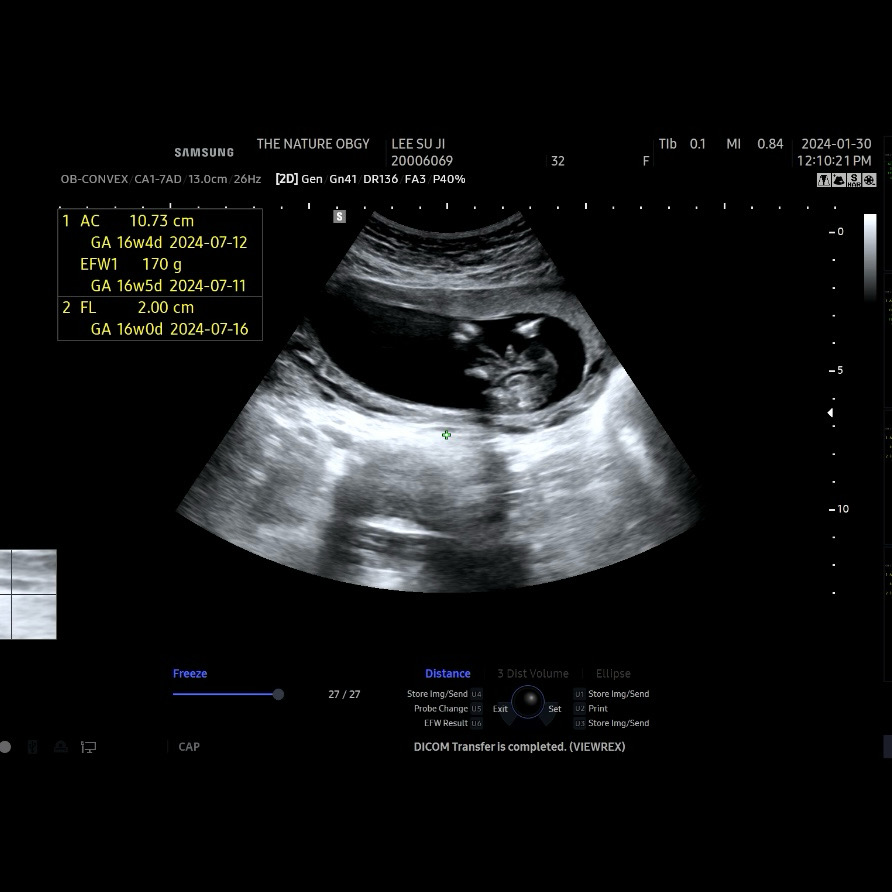

성별 한번만 봐주세요 ㅎㅎ

탯줄은 아닐까? 하며… 계속 보는중인데.. 성별반전은 없는걸까요? 😅 16주차입니다! 물론 아들이든 딸이든 빼곡히 사랑해줄 자신 있습니다!!! ♥️